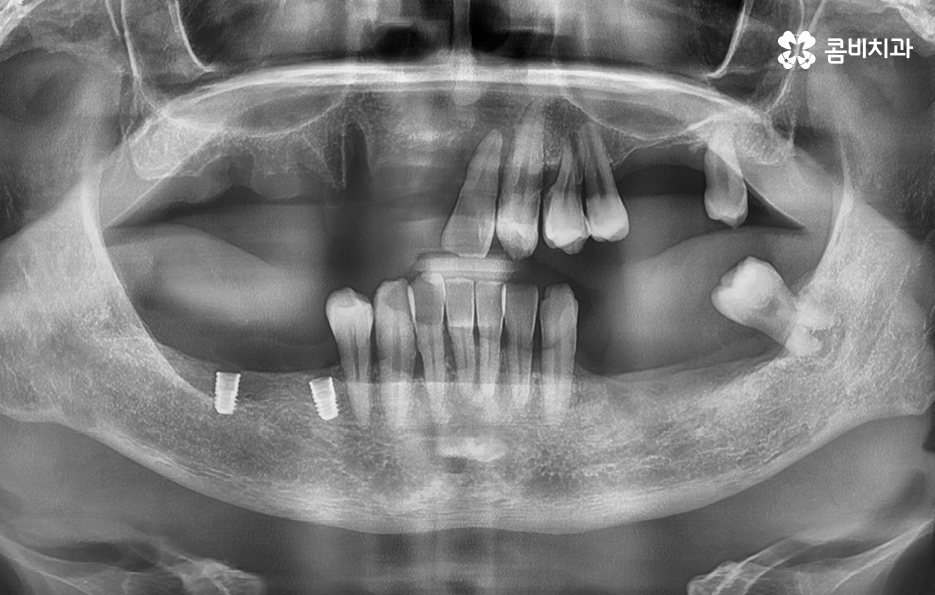

이렇게 여러 원인으로 치아를 상실하면, 그 다음 문제는 어떻게 기능을 회복할 것인가 중요한데 이때 많은 고령층이 비용 부담 때문에 치료를 미루거나 틀니를 고려하는 경우가 많았지만 국가에서 65세이상 임플란트 건강보험 혜택을 제공하고 있고 이 제도는 단순 지원이 아니라, 고령층의 씹는 능력과 전신 건강을 지키기 위한 중요한 정책이라고 할 수 있었어요.

65세이상 임플란트 건강보험 혜택의 주된 내용은 65세이상 임플란트 개수 평생 2개까지 보험 적용 가능이라는 점으로 본인 부담률 30% 한하여 환자가 치료비를 부담하면 되기 때문에 경제적으로 상당히 큰 혜택이라고 할 수 있어요

다만 여기서 주의해야 할 점은 65세이상 임플란트 개수 평생 2개까지 혜택을 받을 수 있다는 점에서 되도록 자연치아의 건강을 잘 유지하면서 필요한 시점에 혜택을 잘 활용하는 것이 중요하겠고 노년기에 치료를 받아야 한다는 점에서는 잇몸 뼈의 상태 및 전신건강까지 잘 고려할 수 있는 시스템이 잘 갖춰지고 경험 많은 치과의사와 함께 치료 계획을 잘 세워야 하며 건강보험 혜택에서는 뼈이식이나 상악동거상술, 보철물의 변경 같은 추가적인 사항에 대해서는 별도의 비용으로서 치료비를 납부해야 하므로 각 환자분들에게 적합한 치료 계획에 대해 잘 이해하여 치료비 예산을 잘 계획하실 필요가 있었어요.